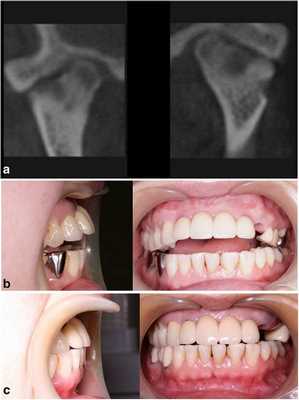

Клинический случай 1

52-летний мужчина обратился за помощью по причине нарушения прикуса после кондилэктомии. Он упал вниз по лестнице и сломал нижнюю челюсть в области шейки суставного отростка. В больнице ему провели открытую редукцию поврежденной области с фиксацией частей сустава. После операции произошло инфицирование области правого ВНЧС, из-за чего пришлось провести удаление суставного отростка. Через месяц после оперативного вмешательства он обратился за помощью в стоматологическую клинику Университета Йонсей. В состояние покоя его нижняя челюсть была смещена вправо, а окклюзионное соотношение челюстей было нарушено вследствие кондилэктомии (фото 1а).

Фото 1.

а) Смещение нижней челюсти вправо (зеленая линия) в результате кондилэктомии (желтый круг).

b) Панорамная рентгенограмма, полученная через 1 день после операции, продемонстрировала восстановление окклюзионного соотношения (зеленая линия). Для стабилизации окклюзии во время операции были использованы межчелюстные фиксационные винты.

Диапазон раскрытия рта был ограничен расстоянием в 30 мм. После назначения пероральных антибиотиков с целью обеспечения инфекционного контроля была запланирована операция по реконструкции правого ВНЧС с использованием суставного протеза. Во время операции хирурги обеспечивали стабилизацию окклюзии путем межчелюстной фиксации для восстановления первоначального соотношения верхней и нижней челюстей. Установку суставного протеза проводили через два разреза: один – в околоушной области, другой – в подчелюстной по Risdon. Панорамная рентгенограмма, полученная через день после операции, подтвердила восстановление нормального окклюзионного соотношения (фото 1b). Через 3 дня пациента выписали без каких-либо осложнений послеоперационных осложнений, обеспечивая наблюдение на протяжении одного года. Протез функционировал достаточно хорошо, а восстановленная окклюзия оставалась стабильной, хотя максимальное открытие полости рта так и не удалось увеличить более чем до 30 мм.